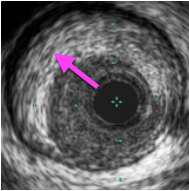

解離病変のIVUS画像は、プラーク部分に切れ目がはいっているのが特徴だ!

解離とは、血管に亀裂が入っている状態で

バルーン拡張やガイドワイヤー、ガイディングカテーテルで血管を傷つけることで起こる合併症だ。

解離を放置しておくと、亀裂部分から血液が侵入し、血腫ができる可能性がある。

解離を発見したら、解離部分にステントを留置し亀裂部分を押さえつける必要があるぞ!